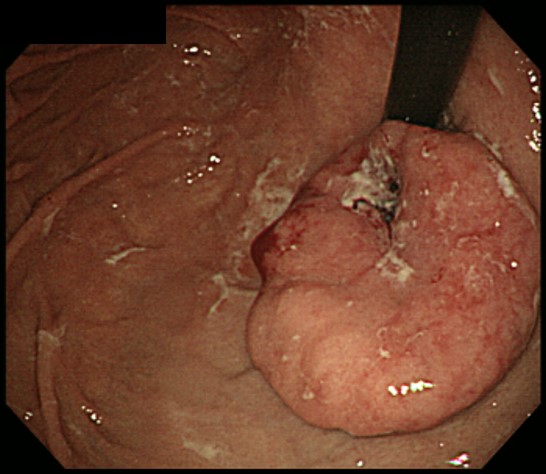

胃ポリープ

粘膜のできもので、多くは隆起性です。ほとんどは、胃底腺ポリープと過形成ポリープです。胃底腺ポリープはピロリ菌感染がない場合にできやすく、胃がんに進行することはほとんどありません。過形成ポリープは、ピロリ菌感染があると生じやすく、内視鏡で観察すると表面が赤く、デコボコしていることもあります。大きくなると出血や貧血を起こすことがあり、がんを合併する可能性があります。ピロリ菌の除菌治療でポリープが縮小することがあるため、それによって内視鏡による切除が可能になるケースもあります。